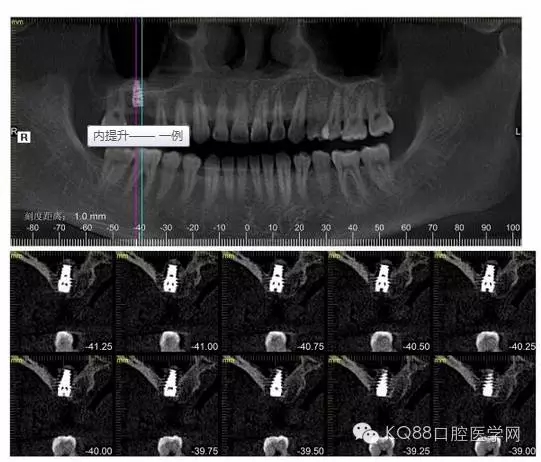

下面是拔牙后三個(gè)月的CBCT。垂直骨高度約6.7mm。

另外一個(gè)切面。垂直骨高度不夠,準(zhǔn)備 :做內(nèi)提升,植骨,植入植體。